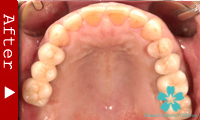

数本の歯を失った場合

この場合もインプラントが理想的な解決法となります。数本のインプラントを歯のない部分に入れ、これを土台としてヘッド部にブリッジをかぶせます。